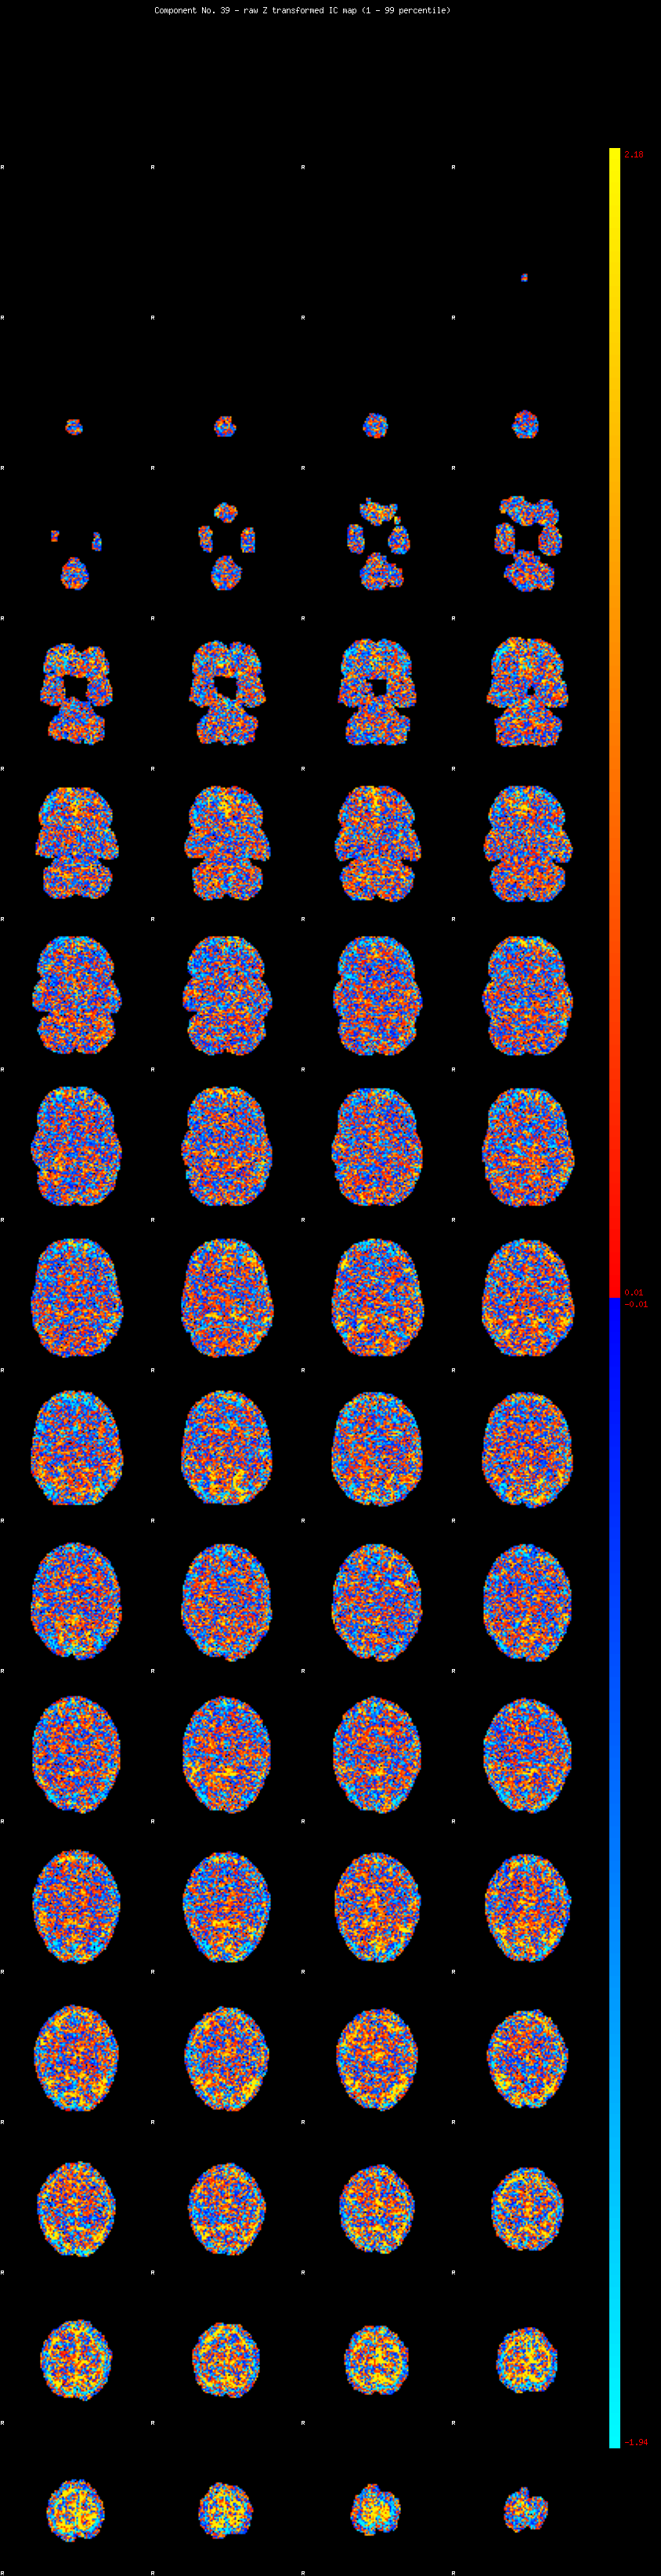

IC_39 Mixture Model fit

Means : 0.000000 2.493582 -2.361725

Vars : 1.000000 1.975249 1.050871

Prop. : 0.919924 0.052080 0.027996